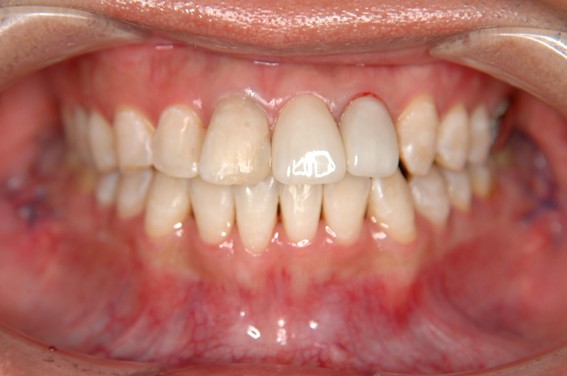

| 主訴 | 前歯が逆に噛んでいる。 |

| 治療内容 | 表側ワイヤー矯正、ジルコニア補綴を行いました。 |

| 治療費 | ワイヤー矯正660,000円(税込) ジルコニア176,000円(88,000円×2歯)(税込) |

| 治療期間 | 30ヶ月 |

| 治療回数 | 30回 |

| 想定されたリスク | 歯根吸収、歯髄壊死、歯髄充血、歯肉退縮のリスクがありました。 |

骨格性Ⅲ級・前歯部反対咬合の症例でした。反対咬合のまま治療していた前歯のサイズ不調和を、表側ワイヤー矯正とプロビジョナルクラウンで調整。正中を整え、犬歯・臼歯ともⅠ級、適切なオーバージェット(上下前歯の前後的な距離)・オーバーバイト(上下前歯の垂直的な重なり)に仕上げました。